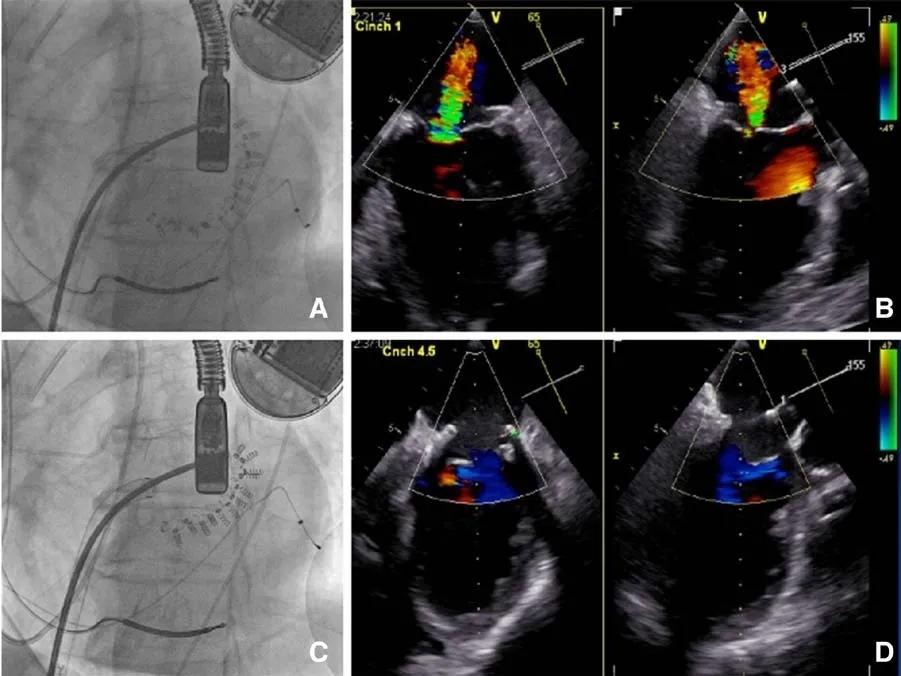

图 9

图 9 Cardioband 的 X 线透视图(A);Cardioband 置入后但还未收紧时,可见严重的二尖瓣反流(B);当装置收紧,使其长度减少 45%时(C),只能探测到极少量残留的二尖瓣反流(D)